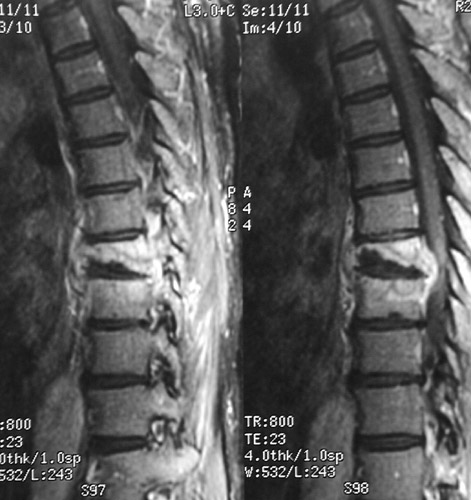

There is bony destruction of T8 and 9 in these two sagittal MRI views in a case of tuberculous osteomyelitis (Pott's disease). The vertebral destruction has resulted in impingement upon the spinal cord.